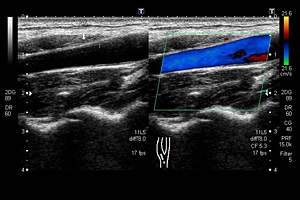

超音波(エコー)検査

超音波検査は、人の耳には聞こえない高い周波数の音波を用いて体内の状態を調べる検査です。目的の臓器に超音波をあて、そこからの反射波をコンピュータ処理して画像化します。一般撮影や、CT検査と違い放射線を用いないので、被ばくの心配がなく装置も小型なので、比較的行いやすい検査です。

しかし、検査の特性上、技術の習得に時間がかかり、結果が技術者の能力に左右されやすいことや、超音波が透過できない空気や骨の影響をうけやすいという欠点もあります。

当院超音波装置(Canon Aplio i700)は2021年4月に導入されました。

当装置は腹部用コンベックスプローブにおいて、唯一マトリックスプローブを採用している装置であり、高画質な画像検査を提供できます。

また、音波の減衰を利用して肝臓の脂肪化(脂肪肝)を定量評価できる機能や、肝線維化(肝硬変)を評価する肝硬度測定(エラストグラフィー)ができるようになりました。両者を併せて評価することにより脂肪肝の病態把握やNASH(非アルコール性脂肪肝炎)の拾い上げ、さらに経時的な病変の進展や改善などの評価に有用となります。

血管エコー検査は、血管の拡張・狭窄・蛇行などの走行状態、血管壁の性状、血流状態(流速・流量)を測定します。動脈硬化の程度が容易にわかるため、心筋梗塞や脳梗塞などのリスク判定などができます。